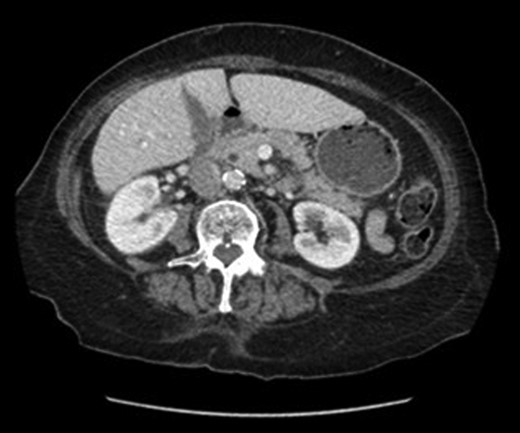

An abdominal ultrasound (Fig. 1) demonstrated a distended gallbladder with multiple subcentimeter gallstones. There was diffuse gallbladder wall thickening up to 7 mm and associated probe tenderness, consistent with cholecystitis. The common bile duct diameter measured up to 7.4 mm without any evidence of choledocholithiasis, thus did not require ERCP. However, the pancreas was not well visualized. A follow-up CT abdomen (Fig. 2) was performed, which demonstrated evidence of pancreatitis with moderate peripancreatic fat stranding without any features of complications including necrosis, abscess or pseudocyst.

Ultrasound image of cholecystitis demonstrating thickened gallbladder wall.